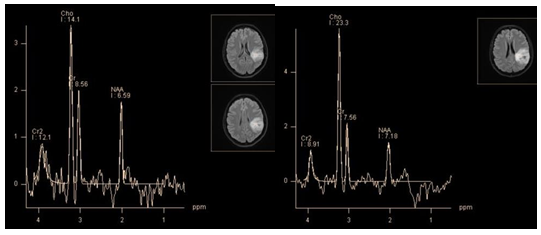

The general rule for metabolite profile of all gliomas is reduction of N-acetylaspartate (a marker of neuronal integrity) and increased levels of choline (a marker of cellularity, and membrane turnover), proportional to the degree of malignancy of tumors (Figure 14). But there is an exception of the rule. The most common of benign tumors, pilocytic astrocytoma (grade I), usually shows a very "aggressive" metabolite profile, with a significant reduction of NAA, high level of lactate and relative increase of choline (Figure 15). According to Hwang et al. the typical rate of main metabolites of pilocytic astrocytomas is Cho/NAA - 3.40, Cho/Cr - 3.46. The main difference between the profiles of pilocytic astrocytoma and malignant neuro epithelial tumor is the absence of a dominant lipid peak.35

Figure 14 Glioma follow-up PRESS, TE 135 ms. First discovered glioma, showing a moderate decrease in NAA and increased Cho levels, which is a typical profile of metabolites for benign (grade II) glioma (a). Observation after 2 years of the same tumor (b). Tumor size did not change significantly, but ratio of Cho/NAA and Cho/Cr is highly suggestive of malignization, a transition to grade III.

Figure 15 Pilocytic astrocytoma (grade I), PRESS, TE 30 ms (a) and PRESS, TE 135 ms (b). Both sequences demonstrate a high lactate doublet, a significant decrease in NAA and Cr, as well as a high Cho level. This "aggressive" metabolite profile is rather typical for this histologic type.